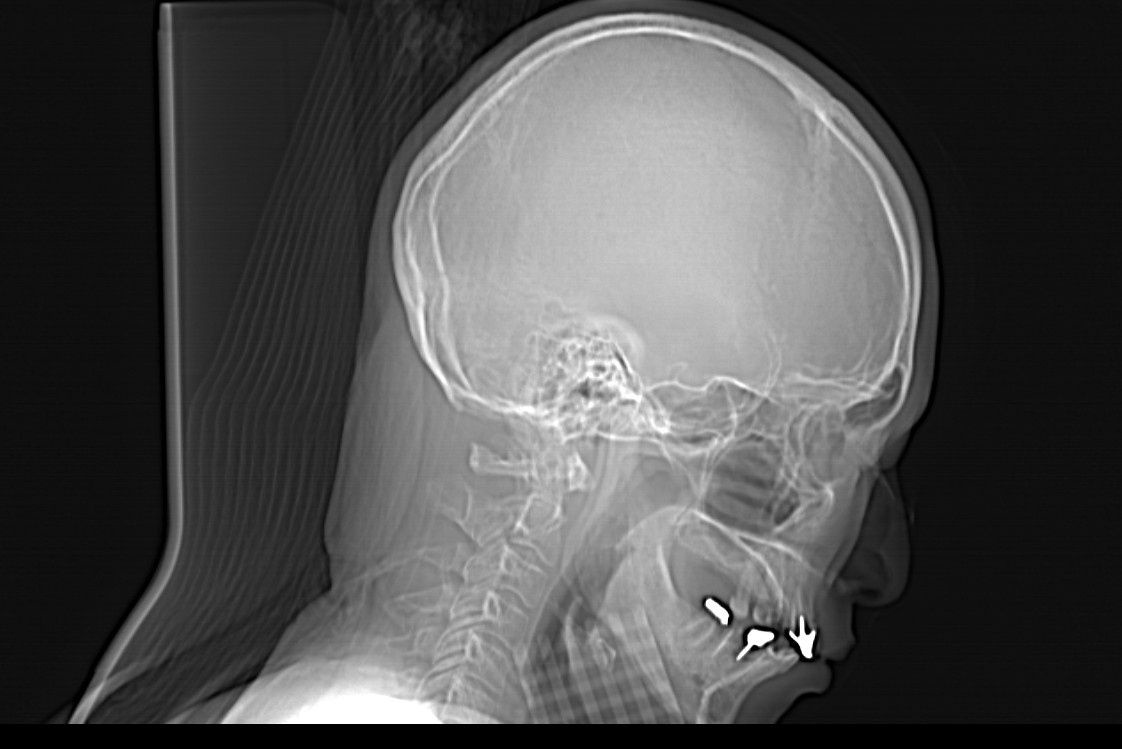

魚の骨(アジ)が刺さったんだけど医者に行っても見当たらない、CT撮ってもこれは魚の骨じゃないって言われるんだよ

でも10月に刺さってからずっとしゃべりにくいし食事も柔らかくしないと喉を通らないんだよ

常に喉をチクッと刺す感じ

有識者から診てどう見えるかな?

そうCTに写っている位置と痛みがある位置が感覚では一致してる

でもこんなところに魚の骨があるわけないって言われて取る形もしてもらえないんだ…

奥にズズッと行く感覚があるから

おそらく最初は外から見えている位置にあったんだと思うけど見てもらう頃には粘膜に埋まってしまって見えなくなったんじゃないかと思う

今日も紹介状をもらった大病院でこの画像を見せたんだけど「魚の骨じゃないですね」って言われた

それで終わらせられそうになったからなんとか色んな断面で頭部を撮ってほしいってお願いしてなんとか撮ってもらえた

で結果を1週間後に2人の専門家に見てもらって結果を聞く